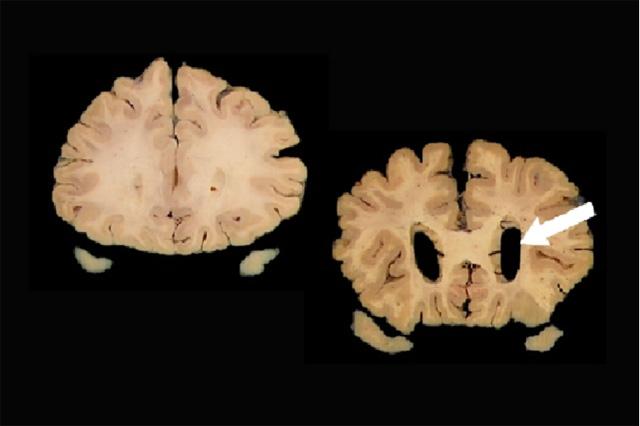

An image taken from a normal brain is shown on the left. Dilation of the ventricles (arrow) in the brain image on the right is a sign of atrophy that CT and MRI scans can measure.